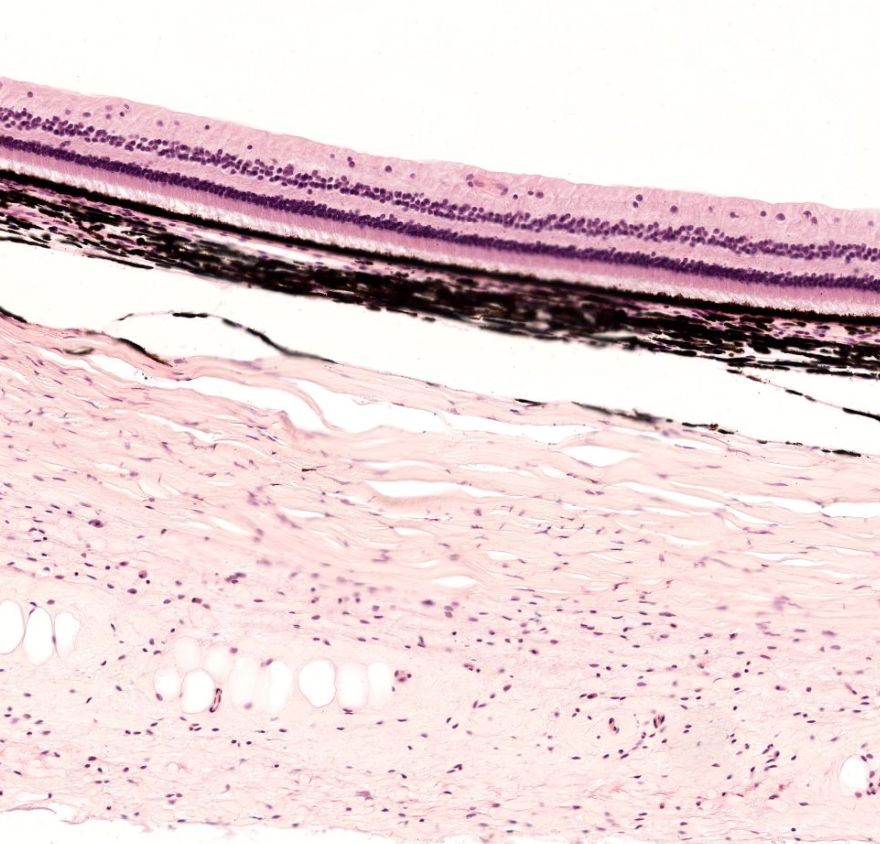

Globo ocular